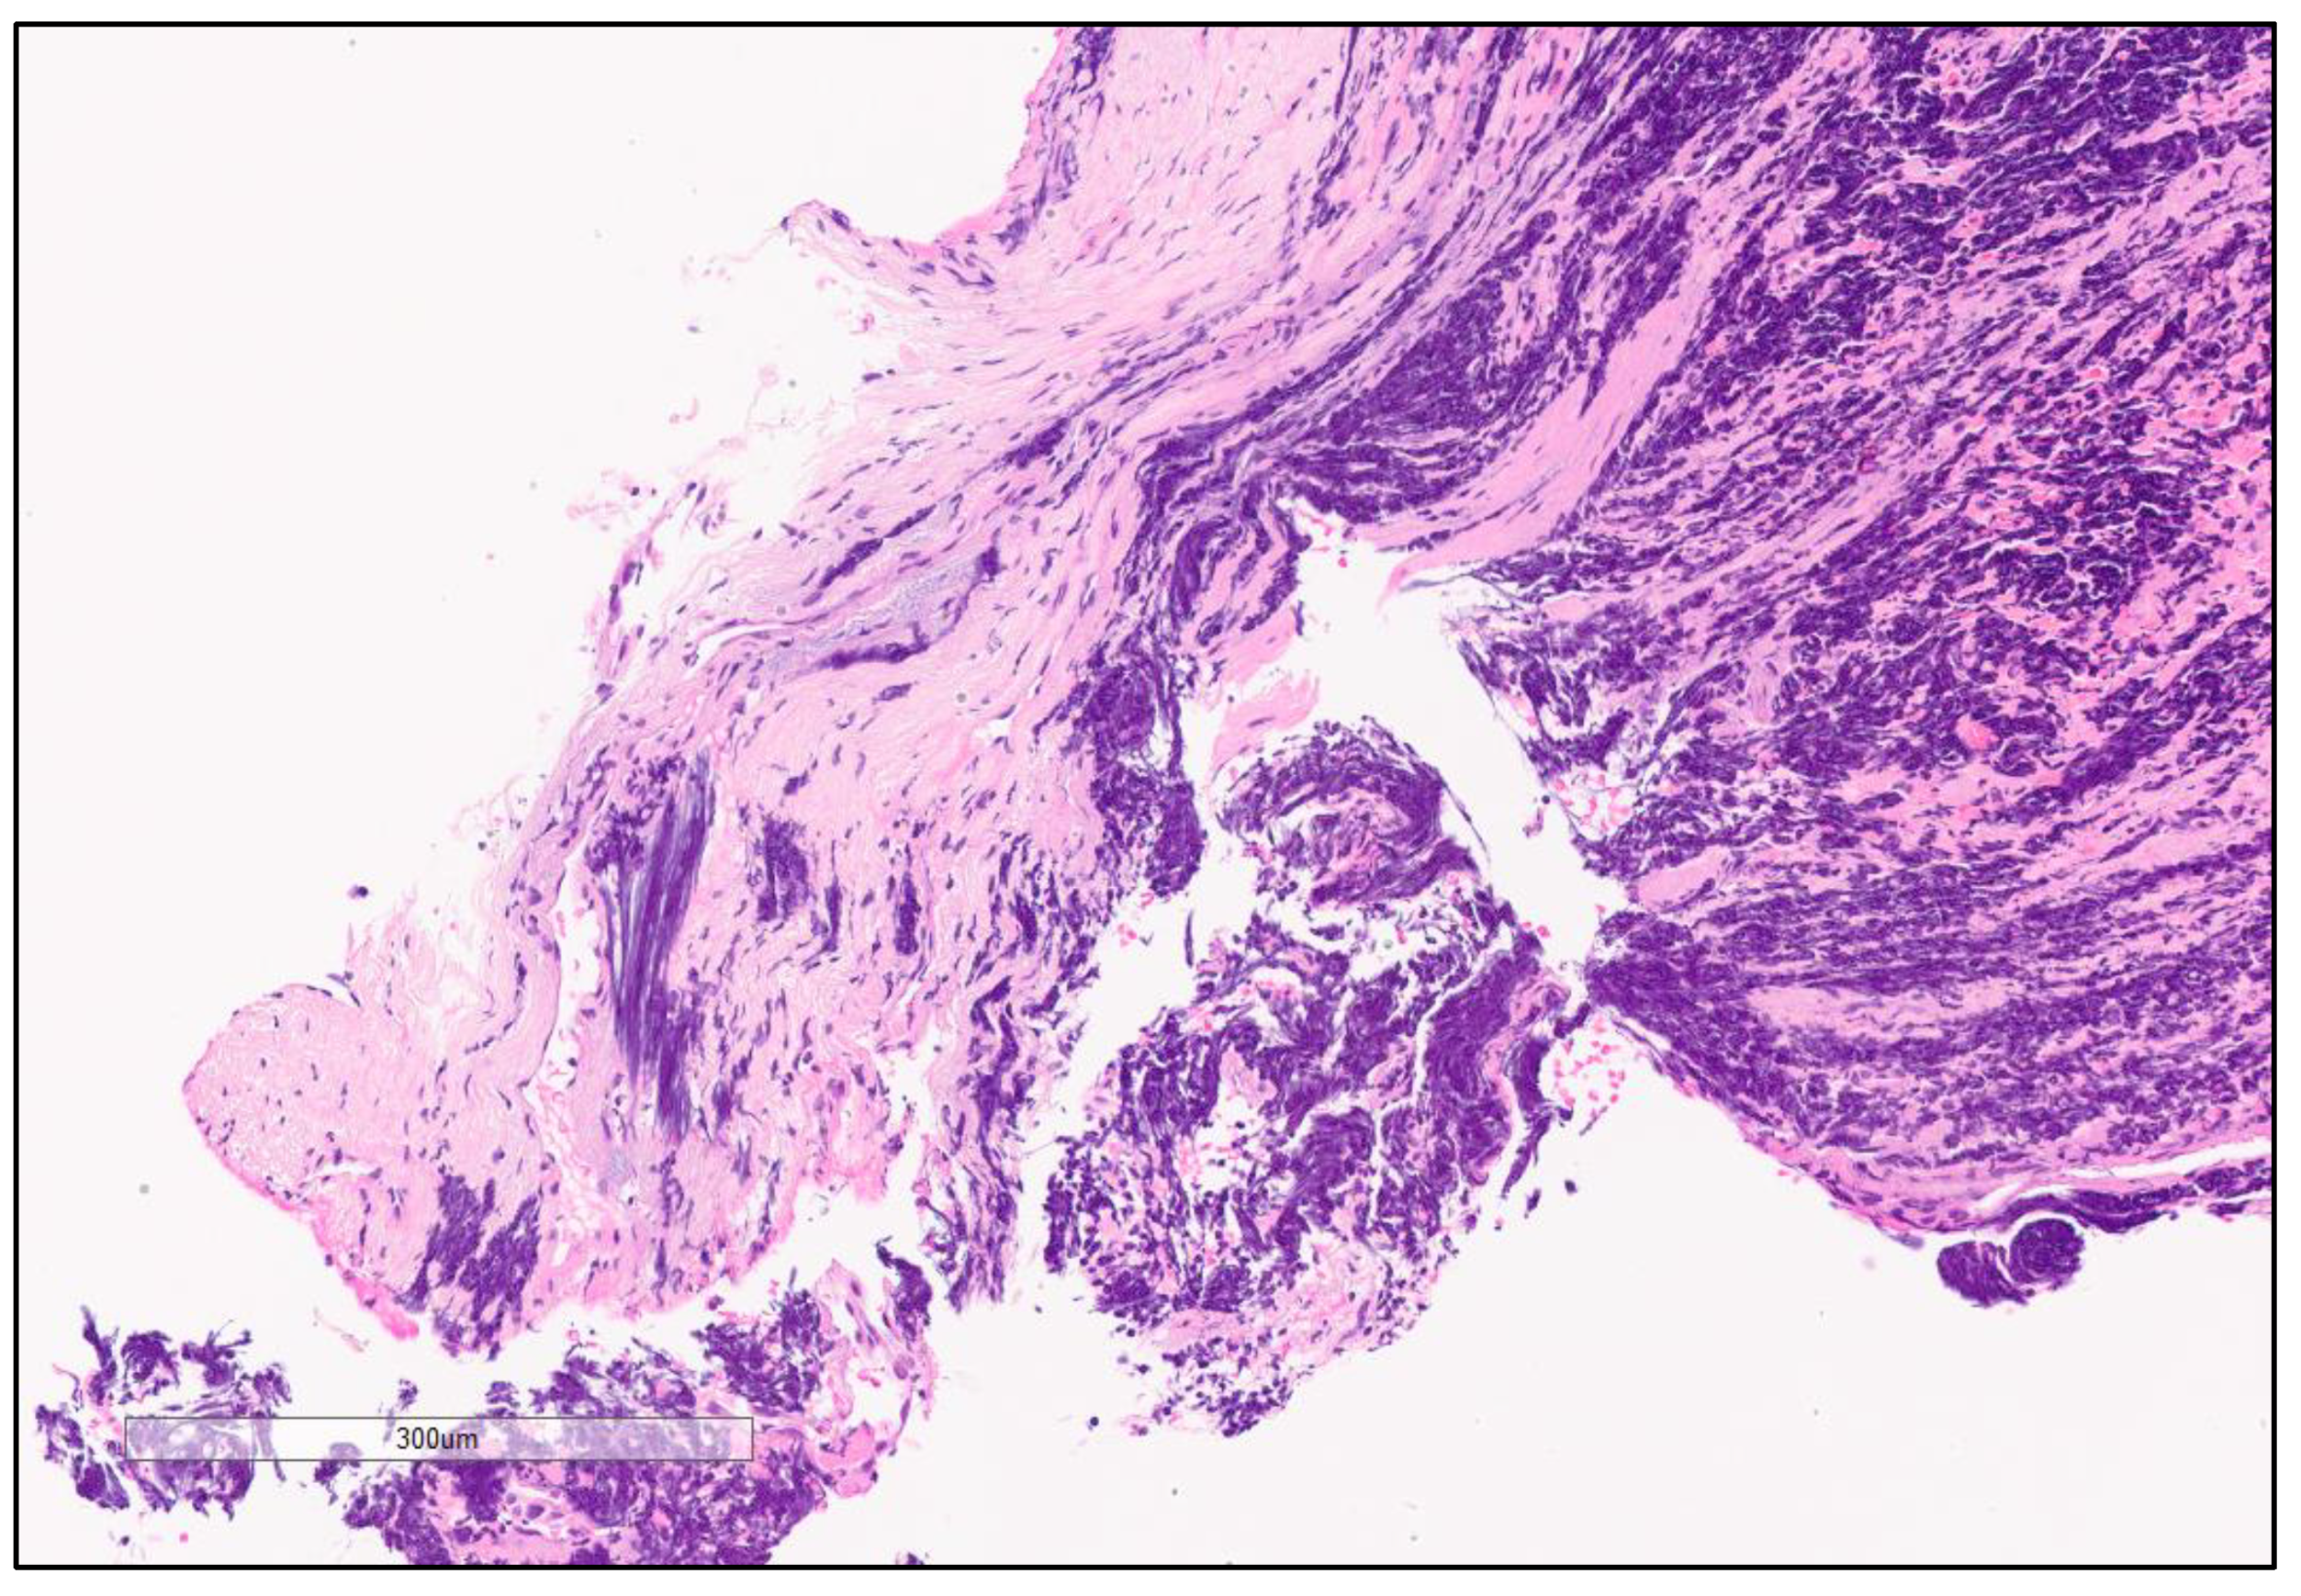

4. Microscopic Features of SCLC

4.2. Histopathological Features